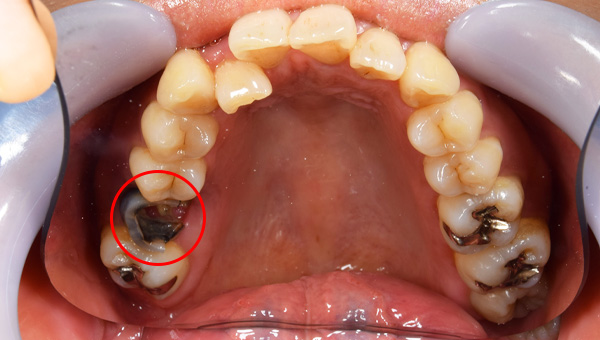

歯が大きく欠けた

歯ぐきが治癒した

説明:

右上の歯が大きく欠けています。黒く虫歯になっているのがわかります。移植を計画しましたので、歯ぐきがしっかり治癒するのを(1ヶ月)待ちました。